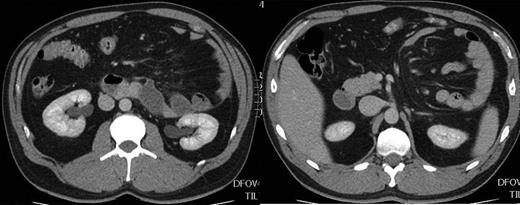

A 35-year-old male presented to accident and emergency with left upper abdominal pain, nausea and loss of appetite for 3 days. On retrospective questioning, he admitted to a propensity to vomit occasionally after large meals dating back to his childhood. On examination his abdomen was mildly distended with tenderness and a mass in his left upper quadrant. Chest and abdominal X-ray were normal. CT scan of the abdomen and pelvis with oral and i.v. contrast showed a left paraduodenal hernia (Fig. 1). Within 24 h his symptoms had resolved spontaneously and he was able to eat freely without pain and was discharged. He had mild left upper quadrant pain on a few occasions over the next 2 weeks and the option of surgical repair was discussed. As 50% or more paraduodenal hernias develop partial or complete small intestinal obstruction, surgical treatment was recommended. The patient decided to proceed to surgical treatment and a minimal access approach was planned.

CT scan of the abdomen demonstrating left paraduodenal hernia.